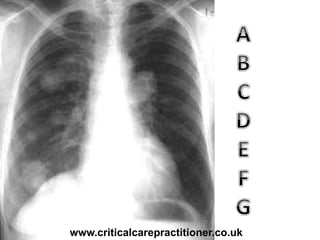

TECHNICALS

AIRWAY

BONES

cARDIAC

DIAPHRAGM

GASTRIC BUBBLE

EQUAL LUNG FIELDS

Rotation?

Penetration?